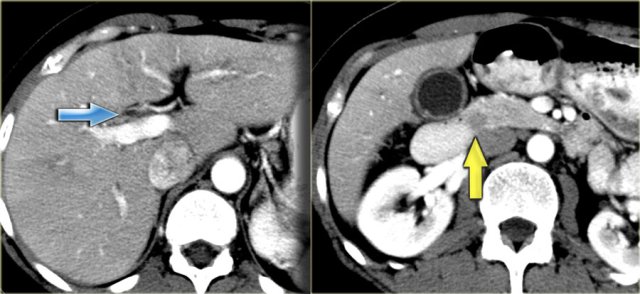

On the left we see images of a patient with Caroli disease.

Notice the intrahepatic duct dilatation and the normal caliber of the choledochal duct (extrahepatic bile duct).

The hallmark of Caroli disease is intrahepatic duct dilatation.

The dilatation can be very large and saccular as seen in the case on the left or it can be very linear.

On the left a patient with dilated bile ducts with intraductal stones (arrow)

Study the image on the left.

Then continue reading.

The findings are:

- Medullary sponge kidney with stone formation (red arrow)

- Mild bile duct dilatation (blue arrow)

- Round hypoattenuating mass in the right liver lobe

The mass in the right lobe of the liver turned out to be an abscess.

Remember that liver abscesses in the early phase can look quite solid.

In the differential diagnosis we would also have to include a neoplasm, because patients with Caroli disease have an increased risk of developing a cholangiocarcinoma.